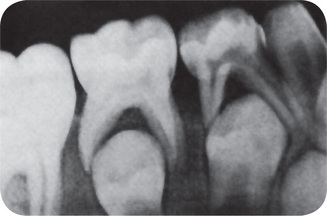

Characteristically, there is histologic evidence of widespread formation of globular, hypocalcified dentin, with clefts and tubular defects occurring in the region of the pulp horns. In addition, these pulp horns are elongated and extend high, often reaching nearly to the dentinoenamel junction. This may even be evident on the radiograph (Fig. 15-9). Because of these defects, there is commonly invasion of the pulp by microorganisms without demonstrable destruction of the tubular matrix. Following this, there is often periapical involvement of grossly normal-appearing deciduous or permanent teeth, followed by the development of multiple gingival fistulas. In addition to abnormal cementum, the lamina dura around the teeth is also reported to be frequently absent or poorly defined on the radiograph, and the alveolar bone pattern is often abnormal.

Figure 15-9 Vitamin D-resistant rickets in a boy six years of age.

The full mouth radiographs (A) show the wide root canals and pulp chambers. A ground section of an incisor tooth (B) shows the interglobular nature of the dentin. The deciduous molar (C) when split shows the relatively small quantity of dentin as well as the poor quality of the dentin. Note the connection between the pulp chamber and the occlusal surface of the tooth, a common finding in this disease, accounting for the frequent pulp infection and periapical involvement without the presence of a carious lesion. Courtesy of Dr SS Arnim